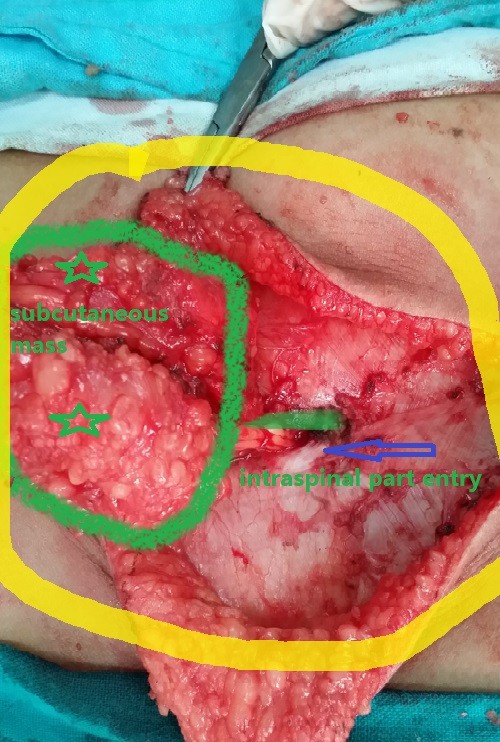

congenital fatty tumor of the spinal cord versus the lumbar vertebrae of a four-year-old girl